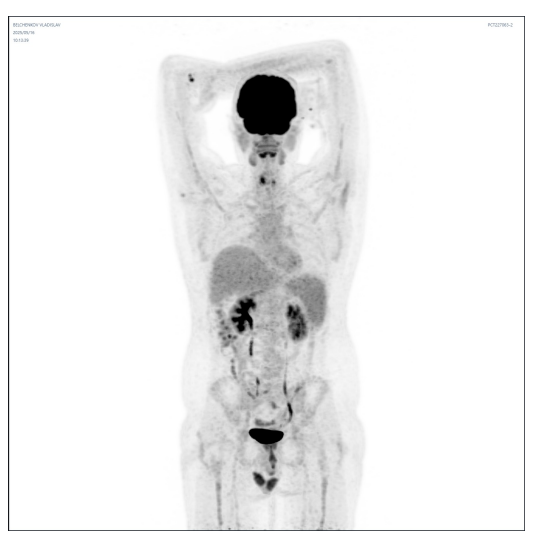

2025 年 3 月 20 日,弗拉迪斯拉夫在陆道培医院国际部工作人员的协调下入住北京陆道培医院。入院后,陆道培医疗淋巴瘤•骨髓瘤中心医生团队迅速为他进行了全面检查,骨穿、腰穿未见明显异常,但 PET/CT 显示纵膈、横隔上下多组淋巴结、肝脏及左肾多发结节,病灶较前增大,代谢较前增高,病情依然严峻。

在肿瘤负荷控制到理想状态后,4 月 14 日开始进行 FC 方案预处理,为 CAR-T 细胞回输做准备。回输后针对性应用 PD-1 单抗增强 CART 扩增和疗效。令人惊喜的是,整个治疗过程仅出现 1 级细胞因子风暴(CRS),未发生神经毒性反应。2025 年 5 月复查 PET-CT 显示所有病灶代谢完全消退,Deauville 评分 1 分。这一结果令患者和家属欣喜若狂,也标志着此次治疗取得了阶段性的巨大成功。